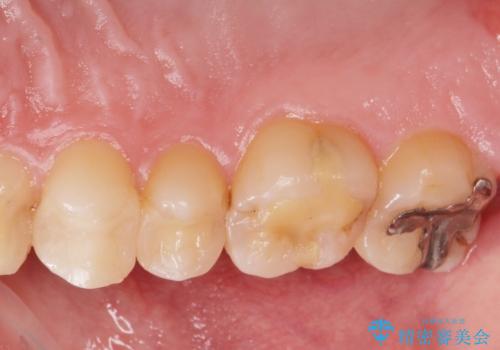

- 銀の詰め物をやりかえたいとの事で来院。

詰め物を外し、虫歯がない事を確認してからe-maxインレーで治療しました。

- e-maxインレー 7.7万円 費用は治療当時の料金となります

白く、適合の良い詰め物が入りました。セラミックは汚れや細菌付着しにくいので虫歯の再発のリスクが低くなります。